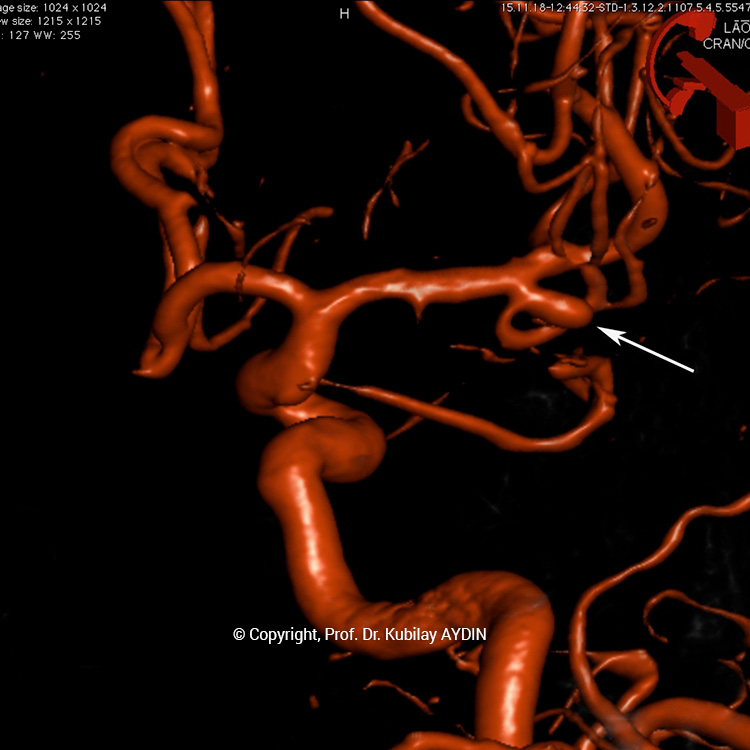

Akım yönledirme tekniği, diğer bir kapalı anevrizma tedavi yöntemidir. Bu teknikte, diğer yöntemlerden farklı olarak, anevrizma koillerle doldurulmaz. Bu yöntemde, anevrizmanın bulunduğu damar içine kan akımını yönlendirme yeteneğine sahip özel stentler yerleştirilir. Bu stentlere “akım çevrici stentler” adını veriyoruz. Akım çevrici stentler, çok sık örgü yapısına sahip metal kafeslerdir. Akım çevrici stentlerin duvarında diğer stentlere oranla çok daha az sayıda gözenek, daha fazla metal tel bulunmaktadır. Bu yapısal özellikleri sayesinde akım çevirici stentler, damar içindeki kan akımını yeniden yönlendirebilme yeteneğine sahiptirler.

Hızla akan bir nehir yatağının, beton bir setle farklı bir yere yönlendirilmesi gibi, akım çevirici stentler de, kan akımını yönledirirler. Bu yöntemde, stent öncesinde anevrizma kesesi içine doğru olan kan akımı, stent tarafından damar içine yönlendirilir. Akım çevrici stent, nehir üzerine kurulmuş bir baraj seti gibi, damar içinde akan kanın anevrizma içine girmesini engeller. Bu şekilde anevrizma içine giren kan akımını azaltılıp ve kısa süre içinde tamamen durur. İçindeki kan akımı ciddi düzeyde azalan anevrizma, pıhtılaşarak küçülür ve kısa süre içinde yok olur. Son 4-5 yıl öncesine kadar tedavisi imkansız veya çok riski olarak kabul edilen anevrizmaları bile, günümüzde akım çevirici stentler sayesinde yüksek başarı oranlarıyla tedavi edebiliyoruz.